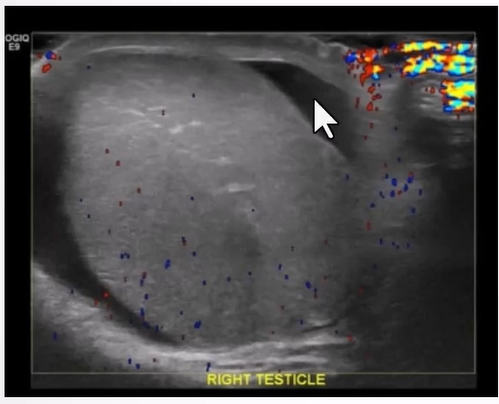

Altered Blood Flow:

Complete torsion - absence of blood flow in both the testis and epididymis

Increased Size of Testis/Epididymis:

Changes in echotexture based on timing post-torsion (homogeneous in early stage, heterogeneous after 24 hours due to necrosis).

Reactive Hydrocele

Scrotal Skin Thickening:

Reactive thickening of the scrotal skin with hyperemia and increase flow on colour doppler